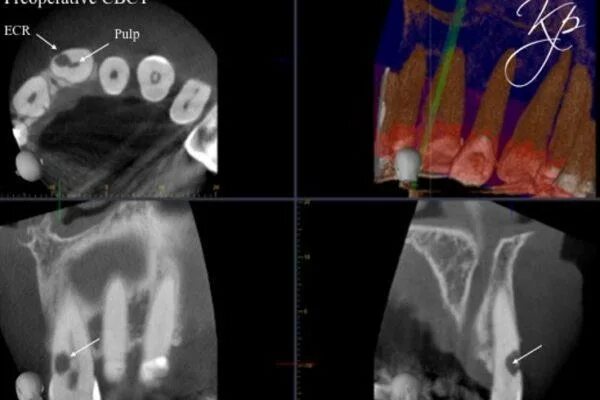

Резорбция епифанов